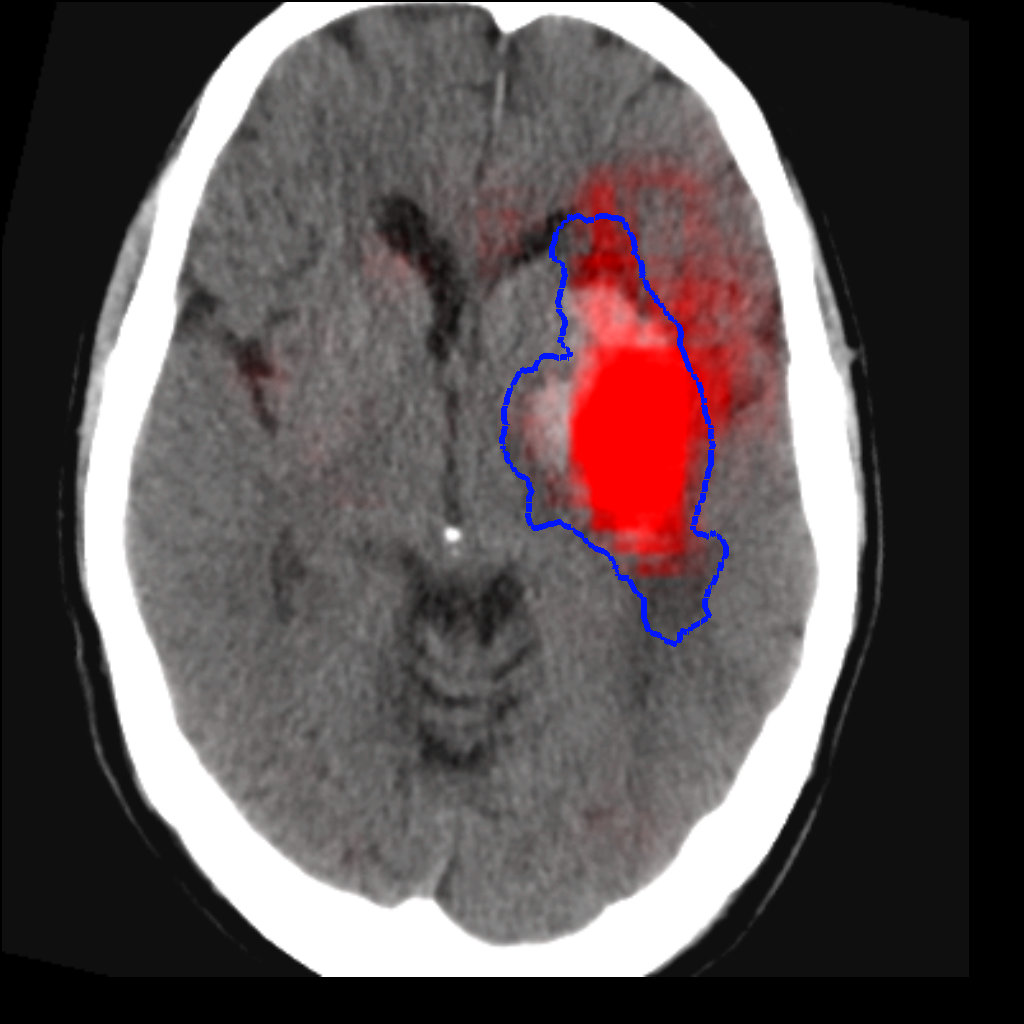

Fig. 3 shows a scatter plot and a Bland-Altman plot of the true and predicted volumes for all subjects in the testing folds using the proposed method. The mean volume error is -2.8 ml (the prediction is a slight underestimation) and the mean absolute volume error is 36.7 ml. The mean Dice score is 0.48. A representative set of predictions is shown in Fig. 4.